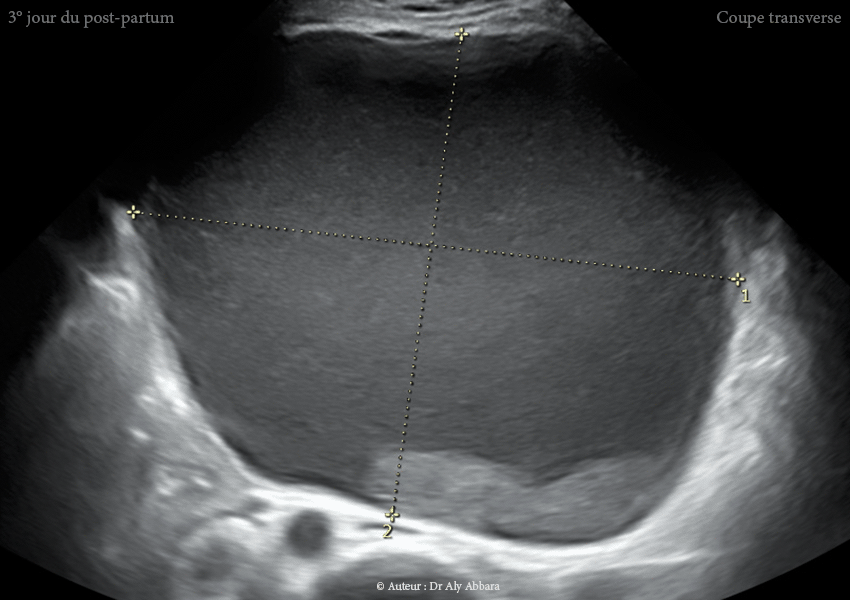

Images échographiques montrant un utérus myomateux portant un myome sous-séreux fundique (classe 7 de la classification FIGO 2011). Images prises au 3ème jour du postpartum après un accouchement par césarienne au terme de 36,5 SA.

Cette régression volumique du myome utérin enkysté s'est poursuivi en postpartum : 1330 cm3 au 3ème jour du postpartum ; 1200 cm3 au 38ème jour du postpartum ; 1119 cm3 au 73ème jour du postpartum et enfin 968 cm3 au 104ème jour du postpartum (~ 15ème jour du postpartum).

Au 3ème jour du postpartum, ce myome apparaît comme une énorme formation kystique de 1330 cm3 de volume, vascularisée et attachée et à la surface extérieure du fond utérin ; son contenu est trouble, liquidien, hypoéchogène avec des plages d'aspect nuageux liées à la présence de résidus flottants (nécrotiques).

• Au jour 3 du postpartum : dégénérescence kystique quasi totale ; décroissance volumique (1330 ml).